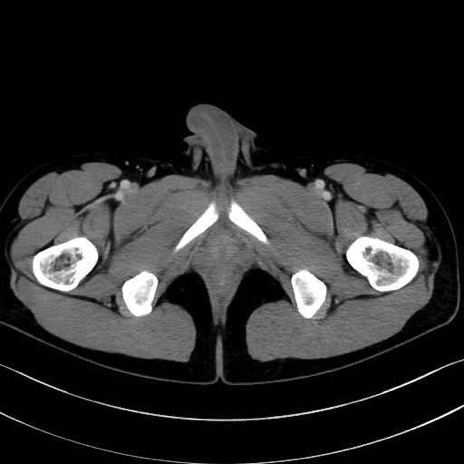

精嚢(seminal vesicle)のCT画像における解剖

症例

【症例】20歳代 男性 スクリーニング